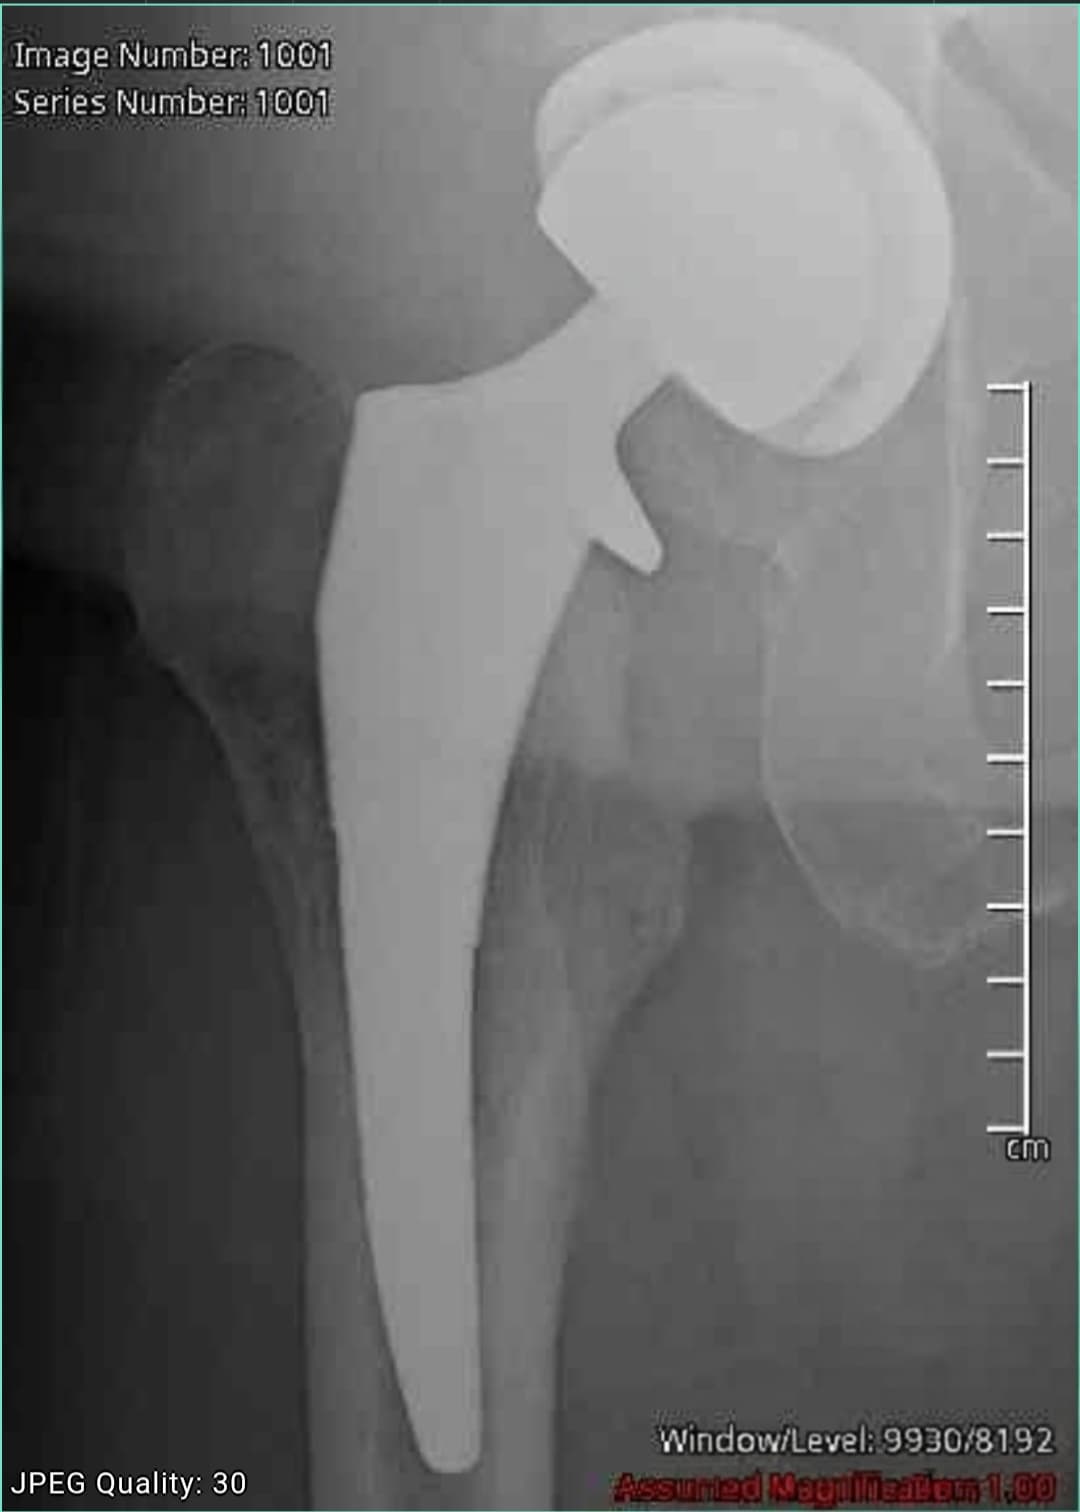

I was always fascinated by health optimization, but it kicked into high gear after a total hip replacement last year. Decades of major pain, then one surgery and everything changed—Patrick and I are way more active, the dogs go everywhere with us, and we’re finally living the life we imagined when we moved to San Diego ten years ago. When something like that gives you your body back, you stop taking it for granted.

Post-op x-ray. Still think it looks like a superhero upgrade.